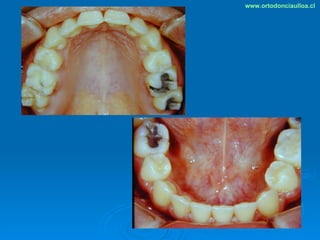

Este documento presenta dos casos clínicos de pacientes que recibieron tratamiento de ortodoncia. El primer caso fue de una paciente femenina de 14 años con apiñamiento dental y mordida cruzada que fue tratada mediante extracción de premolares y alineamiento dental. El segundo caso fue de un paciente masculino de 14 años con clase II esqueletal y desarmonía dentomaxilar que fue tratado con extracción de premolares y corrección de mordida. Ambos casos mostraron mejoría después de 3 años de tratamiento.